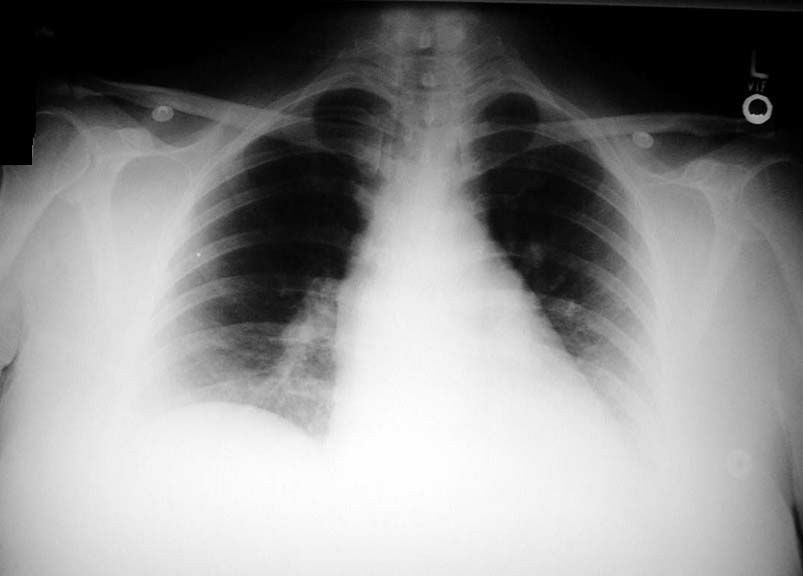

• Nothing specific seen in chest x-ray to make the diagnosis of pulmonary embolism.

• Left diaphragm silhouette is lost, probably due to pleural effusion.

• Ventilation perfusion scans confirm pulmonary embolism.